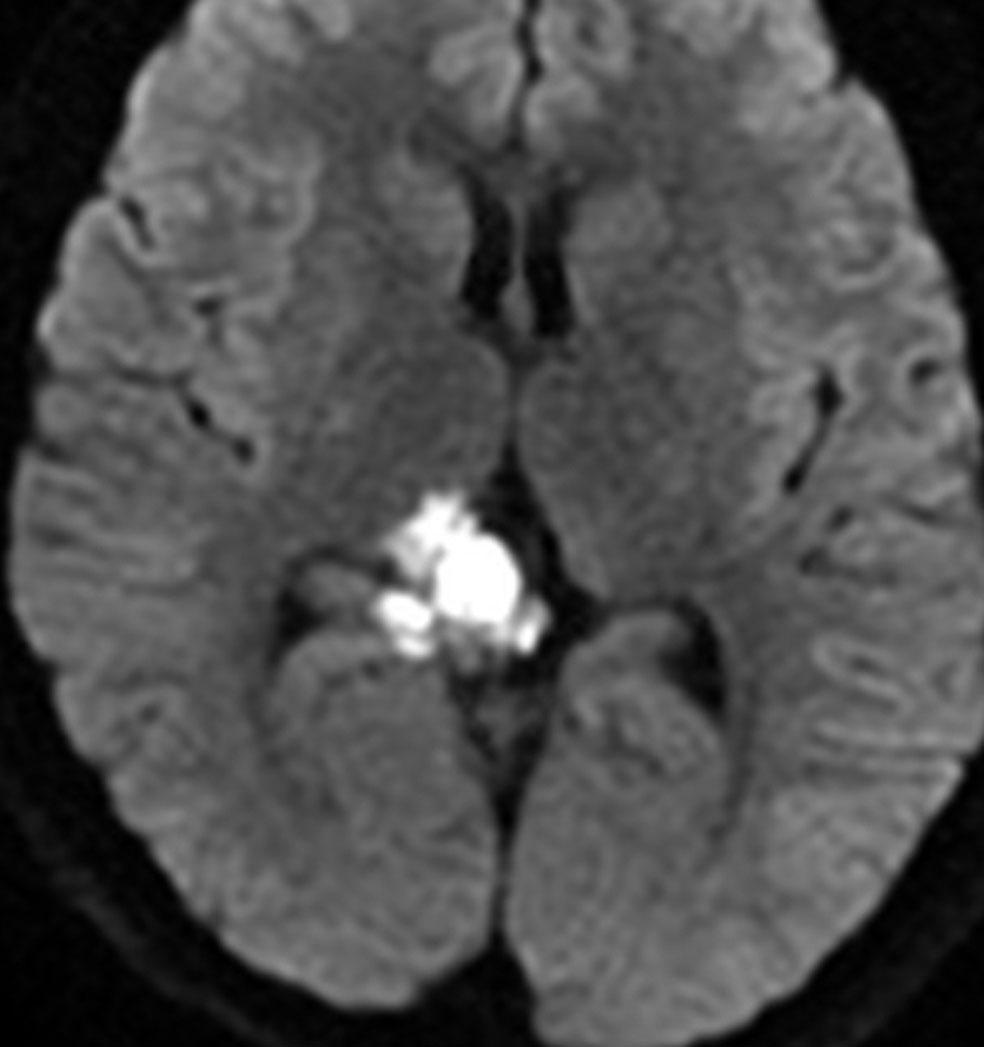

10代で発見された四丘体槽の類表皮のう胞です。左の画像,拡散強調像 DWIで真っ白に見えるので診断できます。真ん中は発見された時のもの,右側の画像は7年後です。ゆっくり増大してきたので,開頭手術(経テント法)で完全摘出しました。周囲の血管や神経に癒着するのでそれほど簡単な手術ではありません。

- でも拡散強調画像MRIで真っ白(高信号)に写りはっきりします

20代の女性が右の激しい顔面痛(三叉神経痛)で発症しました。左から順にMRIのT1強調画像,T2強調画像,拡散強調画像です。髄液と同じように見えますので脳の形の変形だけで腫瘍があることを疑います。でも,拡散強調画像では真っ白になるので腫瘍が存在していることがわかります。三叉神経は腫瘍の真ん中にあって伸びています。

術後の写真です。普通のMRIでは全部取れているかどうかわかりませんが,左の拡散強調画像をみるとおよそ全部取れていることがわかります。でも完全摘出の完全な証明は画像ではできません。術後10年くらい経ちますが再発はありませんでした。